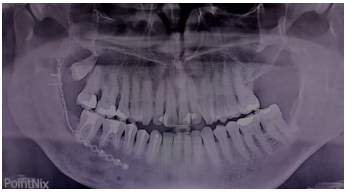

Acudió a servicio de cirugía oral, derivado por su odontólogo, un paciente varón de 65 años sin antecedentes médicos de interés, tras comprobar un importante crecimiento de una imagen radiotransparente respecto a última radiografía de hacía 5 años. El paciente no refirió sintomatología asociada. A la exploración extraoral no se apreció ningún tipo de deformidad ni afectación ganglionar. A la exploración intraoral pese a que se constató la integridad de las corticales, las cuales no estaban abombadas, sí que se pudo apreciar a la palpación un signo positivo de Dupuytren o de “Ping-Pong”. Además se constató una falta de afectación de los dientes del cuarto cuadrante que no presentaban movilidad y tenían una vitalidad positiva (Figura 1). Como complemento a la exploración clínica se solicitó un estudio mediante TAC, donde se apreció la extensión de una lesión radiotransparente que afectaba a rama y cuerpo mandibular derecho. (Figuras 2 y 3).